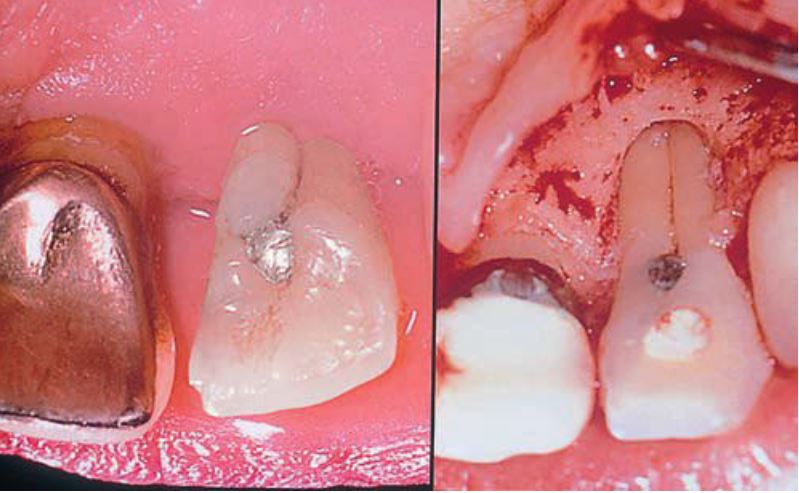

Răng sinh đôi (gemination)

Xảy ra khi một mầm răng có khuynh hướng chia thành 2 răng, nhưng sự phân chia này không hoàn toàn.

Tỉ lệ gặp ở răng sữa cao gấp 5 lần so với răng vĩnh viễn. Răng hay gặp nhất là răng cửa sữa hàm dưới và răng cửa vĩnh viễn hàm trên, bị một bên nhiều hơn hai bên.

Răng sinh đôi cũng hay có rãnh dọc theo mặt ngoài hoặc mặt trong, khía ở rìa cắn. Trên lâm sàng rất khó chẩn đoán phân biệt giữa răng dung hợp với răng sinh đôi.

Trên phim thì thấy răng sinh đôi chỉ có một buồng tủy rất rộng, chân răng to, thân răng chẻ đôi. Tuy vậy vẫn còn nhiều biến thể khác.